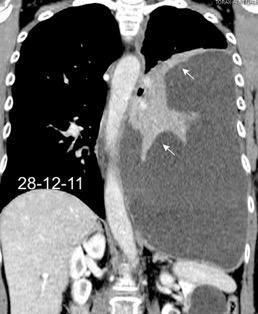

49. INVERSIÓN DIAFRAGMÁTIC. MESOTELIOMA

La ocupación del espacio pleural por derrame (o obstrucción aérea) se acomoda con expansión aumentada de la caja torácica, especialmente en eje vertical. La consecuencia es aplanamiento e incluso inversión diafragmática.

Afzal S, Fatima K, Ambareen M. Antenatal ultrasound diagnosis of congenital high airway obstruction syndrome: a case report and review of literature. Cureus. 2019. Thoma R et al. Physiology of breathlessness associated with pleural effusions. Curr Opin Pulm Med. 2015

Wang JS et al. Changes in pulmonary mechanics and gas exchange after thoracentesis on patients with inversion of a hemidiaphragm secondary to large pleural effusion . Chest 1995

Mesotelioma epitelioide